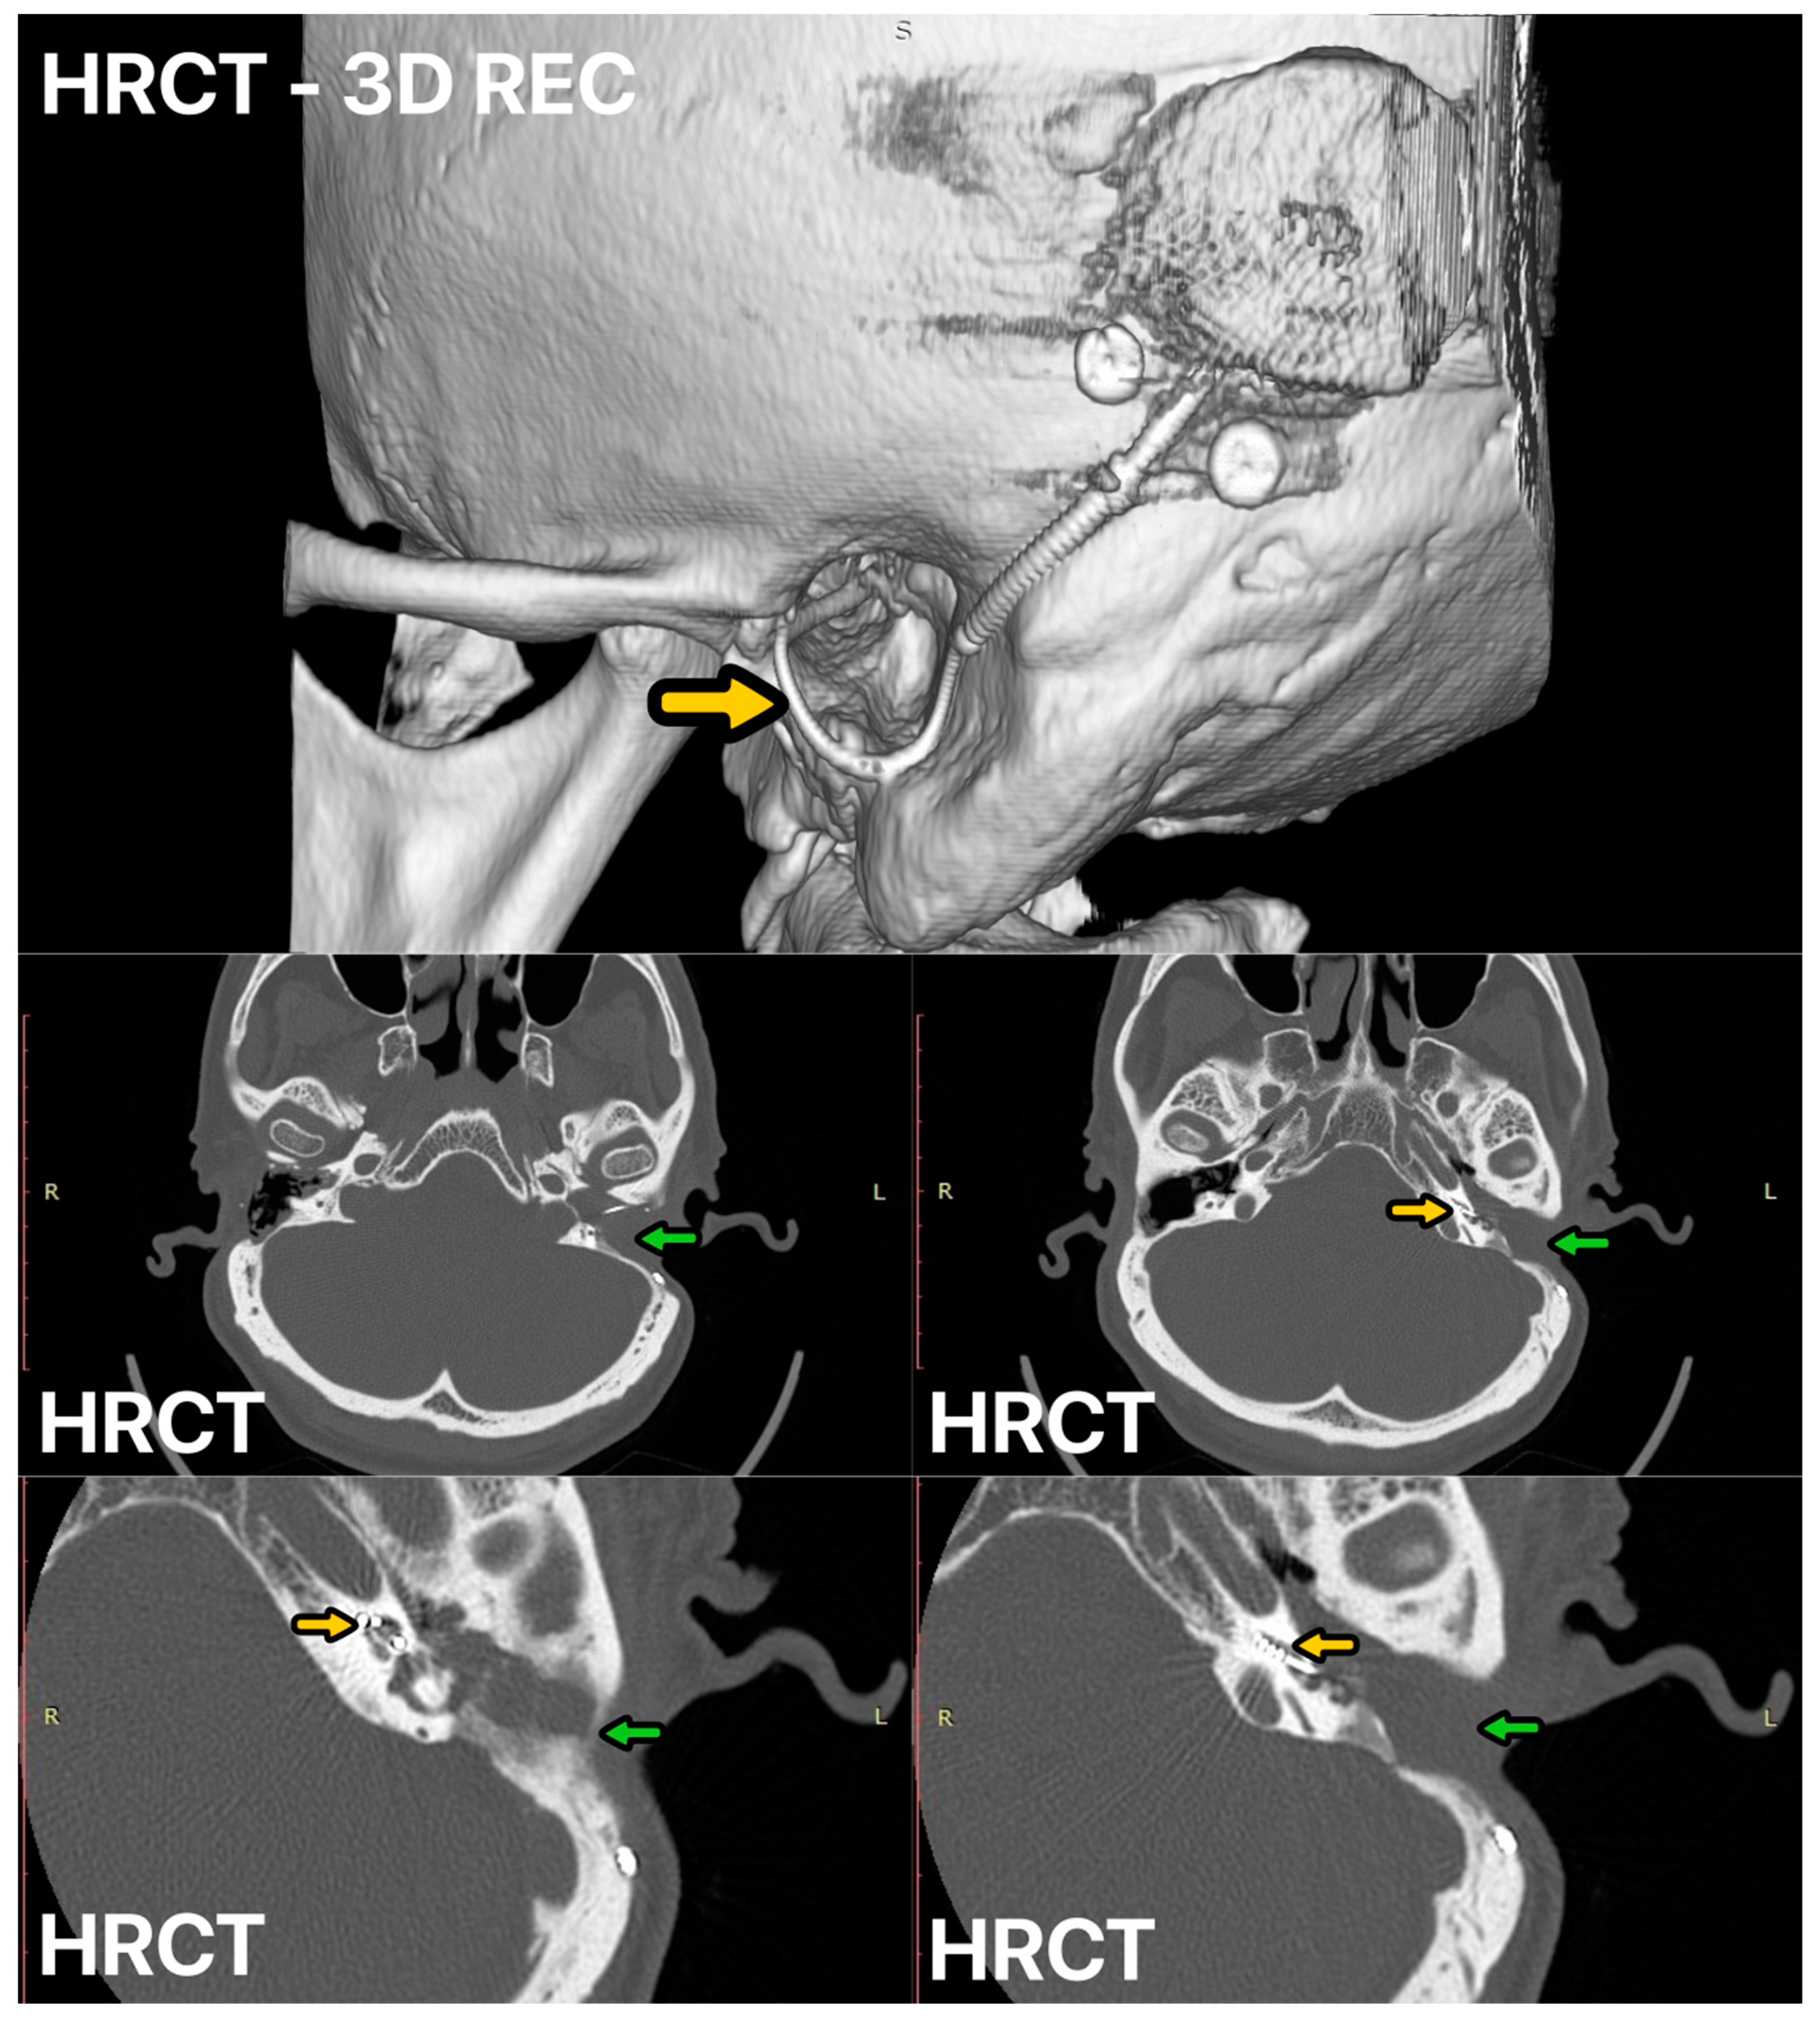

3.1. Case 1